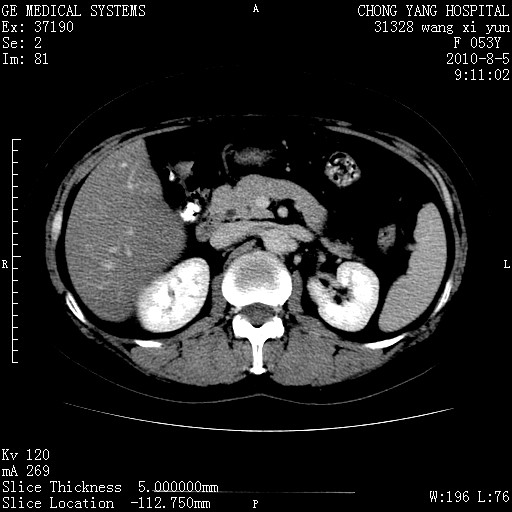

标题: CT28214:F41Y 血尿二十天,建议盆腔平扫加增强。

1)考虑肝左叶胆管细胞癌。2)脂肪肝。